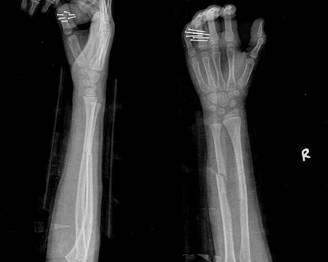

摘要:最新尺橈骨融合方法展現(xiàn)骨頭間的奇妙和諧與友情力量。通過(guò)先進(jìn)的醫(yī)療技術(shù),尺骨和橈骨之間的融合得到顯著改善。這種方法不僅提高了治療效果,還展現(xiàn)了人體骨骼之間的和諧關(guān)系。憑借友情和信念的力量,醫(yī)學(xué)界不斷突破,為患者帶來(lái)福音。

經(jīng)過(guò)醫(yī)生的診斷,小明被確診為尺橈骨融合,這是一種骨骼疾病,會(huì)導(dǎo)致尺骨和橈骨無(wú)法正?;顒?dòng),聽(tīng)到這個(gè)消息后,小明和他的朋友們都感到有些緊張和害怕,但他們并沒(méi)有放棄,而是選擇相互鼓勵(lì),共同面對(duì)這個(gè)挑戰(zhàn)。

在醫(yī)生的介紹下,他們了解到了一種最新的尺橈骨融合治療方法——通過(guò)微創(chuàng)手術(shù)進(jìn)行骨骼融合的新技術(shù),這種方法不僅減少了手術(shù)風(fēng)險(xiǎn),還能更快地恢復(fù)活動(dòng)能力,雖然小明感到害怕,但他的朋友們一直陪伴在他身邊,給予他勇氣和力量。